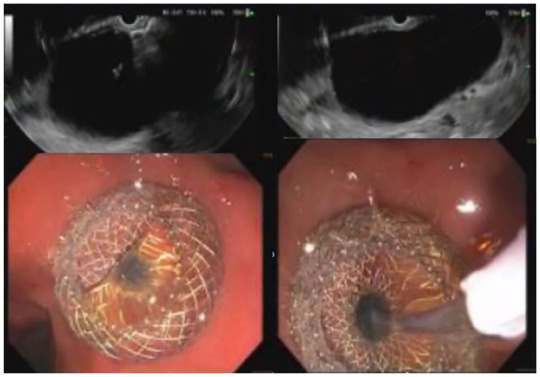

Endoscopic ultrasound-guided drainage of loculated malignancy-related ascites has been reported in limited case series with success in achieving symptomatic relief. In this case report, we detail the successful drainage of a loculated paragastric ascites with insertion of a lumen-apposing metal stent (LAMS) in a patient diagnosed with metastatic ovarian cancer.

Abstract Image